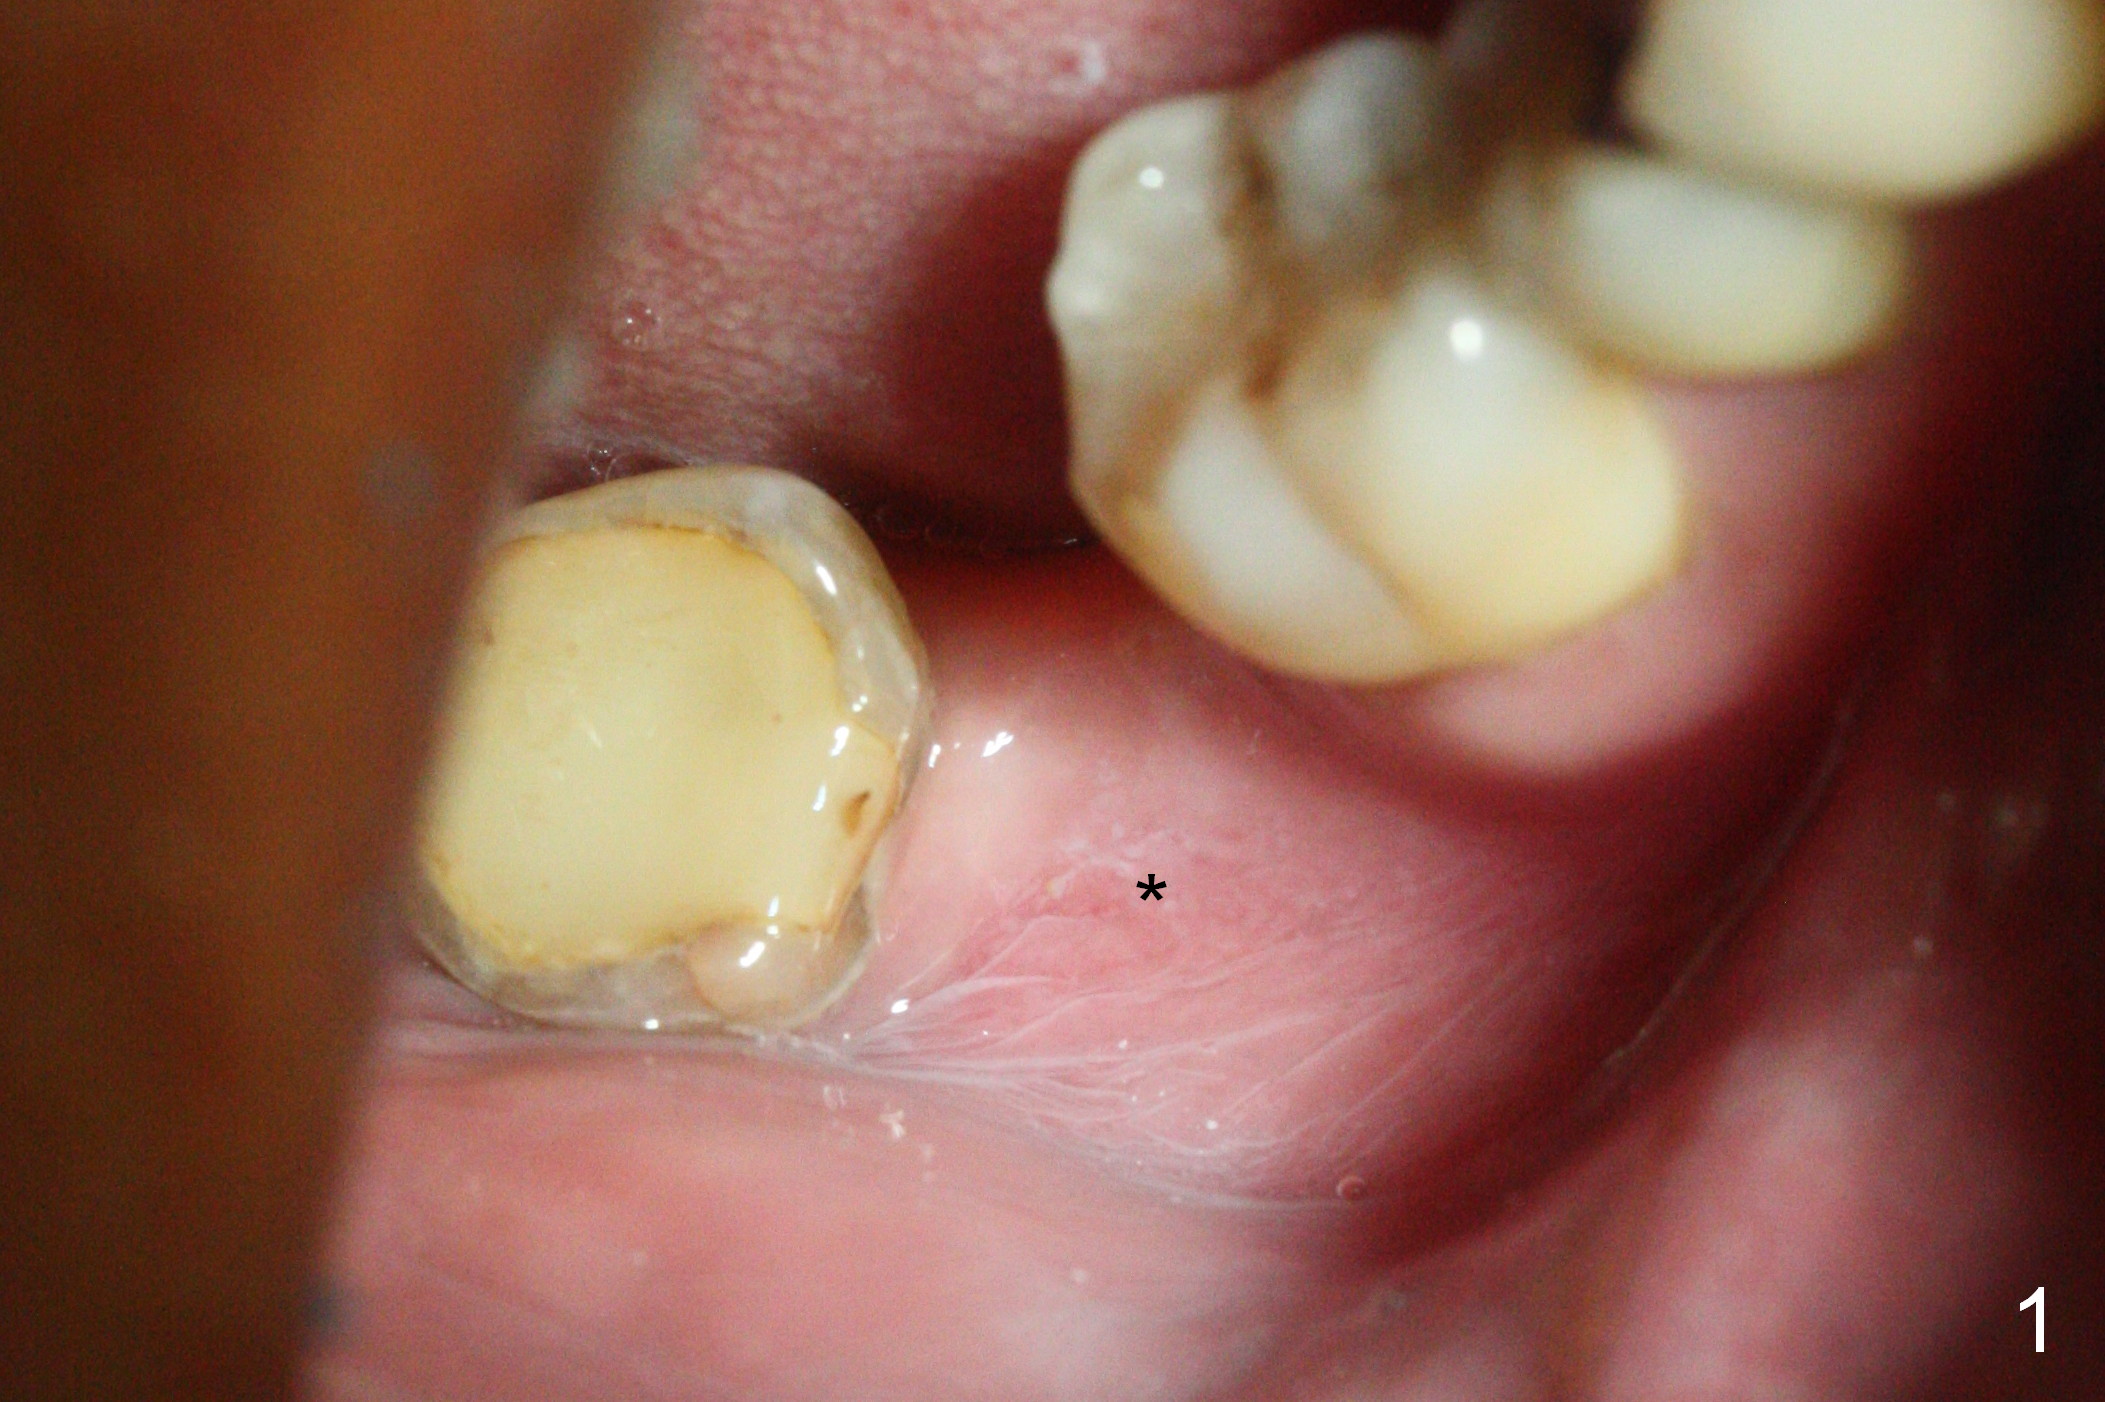

The ridge at #31 is also narrow buccolingually (Fig.1 *).  After incision and 1.6 mm pilot drill, a guide pin with 7 mm length is inserted to confirm trajectory and depth; it appears that 11 mm osteotomy has enough clearance from the superior border of the Inferior Alveolar Canal (IAC, Fig.2 red dashed line).  Following Marking Bur, 3.3 mm Magic Drill and final drill, the buccal plate seems to be thin (Fig.3 *).  When a 4x11 mm IBS implant and 5x4(2) mm pair abutment are placed, the distal thread is exposed (Fig.4 >), the abutment contacts the opposing tooth (data not shown) and there is 2.7 mm clearance from IAC.  After increasing the osteotomy 1-2 mm, the implant is placed deeper; the autogenous bone with Osteogen is placed around the plateau of the implant (Fig.5 >), particularly buccally, followed by collagen membrane.  When sutures are placed around the abutment, the buccal ridge looks bulkier (Fig.6) than preop (Fig.1).  It may remains so long term.  The flap surgery makes it possible for simultaneous GBR and reduction in possibility of peri-implantitis.  Last, periodontal dressing is applied.